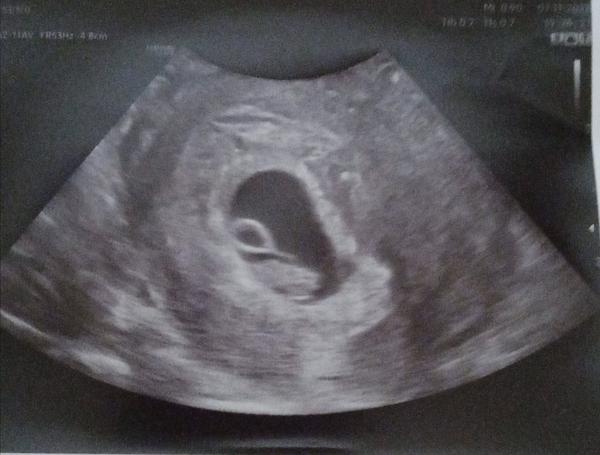

Tady naše malá, 6+5 dle ms dle utz odpovídala 7+0, srdíčko už bilo. Ale já mám třeba krátké cykly, těžko říct kdy se u tebe mimčo zahnizdilo, může být mladší a tím pádem je toho zatím vidět min. Ne testuj, je to blbost, prosperitu těhotenství z toho nezjistís a akorát pro tebe stres. Já blbá se nervila že mám furt na testu 2-3 i v době že bych měla být dávno 3+ a vidíš nakonec byla větší a i srdíčko už tukalo. Pro klid bych šla ještě na hcg ať vidím progres a pak se uklidnit.. Víš stejně teď nemůžeš udělat než mrneti věřit.